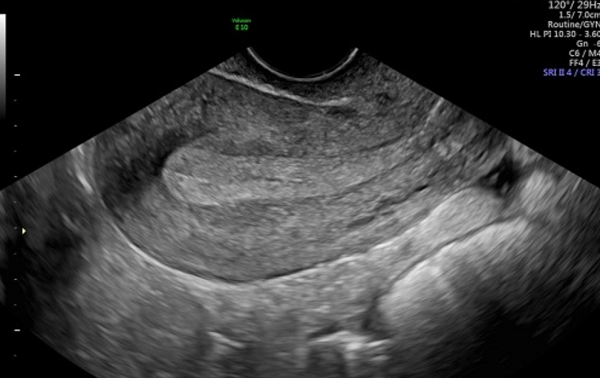

Để có thể biết được chính xác độ dày của tử cung bác sĩ sẽ thực hiện một số phương pháp chẩn đoán như:

- Siêu âm qua ngã âm đạo hoặc siêu âm ổ bụng (với phụ nữ chưa quan hệ tình dục): Máy siêu âm có đầu dò đường âm đạo để đo độ dày của lớp niêm mạc tử cung. Kỹ thuật này an toàn và rất cần thiết trong chẩn đoán các bệnh liên quan đến sản phụ khoa.